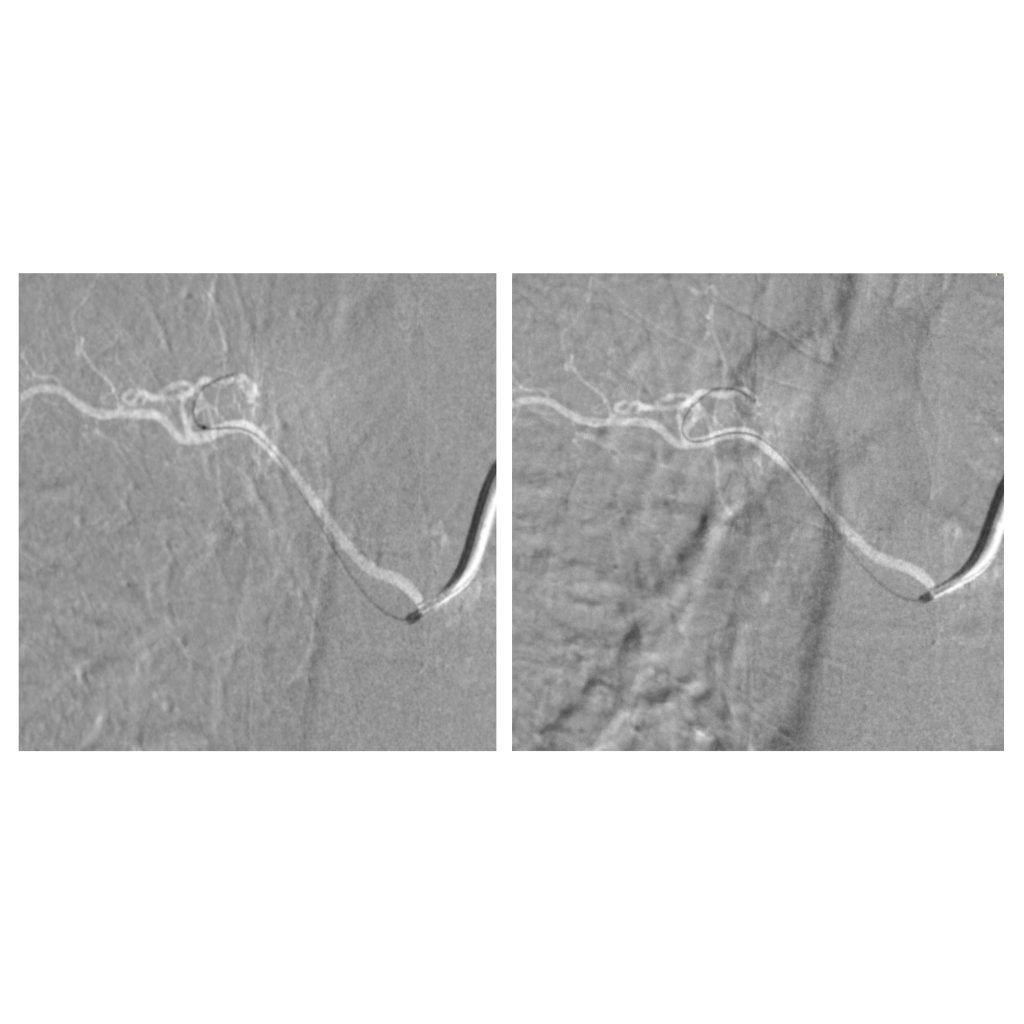

تمكّن الفريق الطبي في وحدة القسطرة بالمستشفى التخصصي، بقيادة الدكتور حازم حبوب استشاري الاشعة التداخلية، من إجراء تداخل طبي متقدم لمعالجة حالة شلل طرفي ناتج عن وجود تشوه شرياني وريدي في النخاع الشوكي، وذلك تحت المراقبة الفسيولوجية العصبية الدقيقة.

وتمت العملية بنجاح من خلال استحضار الإمكانيات الحسية والحركية للمريض أثناء الإجراء، لتفادي أي مضاعفات محتملة.

ويُعد هذا التدخل الأول من نوعه الذي يُنفذ في وحدة القسطرة بالمستشفى، مما يعكس التقدم المستمر في مستوى الرعاية الطبية والتخصصية المقدّمة.